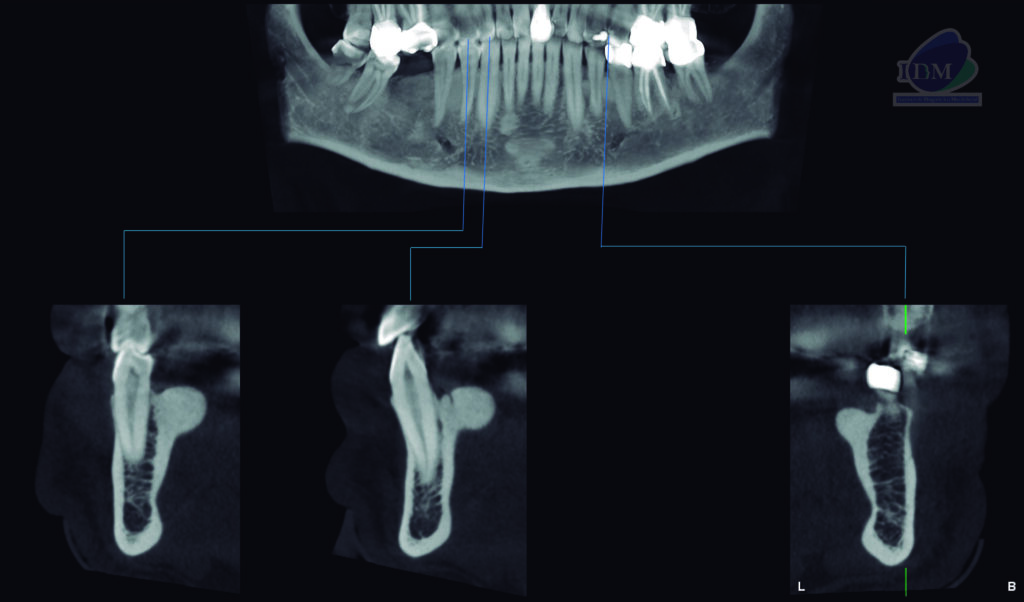

Paciente masculino de 58 años acude al Instituto de Diagnostico Maxilofacial para realizarse una tomografía para la colocación de implantes.

A la evaluación de la tomografía computarizada bimaxilar se observó además de los mencionado, la presencia de imágenes hiperdensas de densidad dentaria de forma irregular ubicadas por lingual, en estrecha relación con la tabla ósea y a nivel de las piezas 34-35 y 44-45 compatibles con torus mandibular.

CORTES TRANSAXIALES